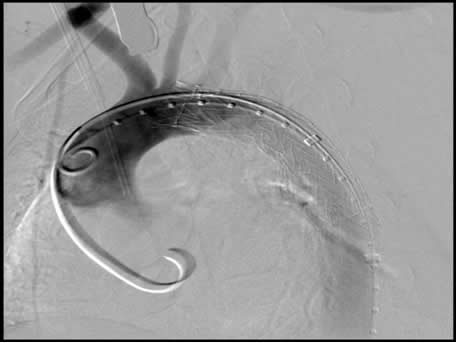

Transcatheter valve-in-valve Implantation With The Edwards

Transcatheter heart valve (THV) implantation with the valve-in-valve (VIV) technique is emerging as a feasible, reproducible and circular landing zone of known diameter (Figure 1). Clinical experience with the VIV technique is ... Access Full Source

P-270 Percutaneous Pulmonary valve Implantation (Melody ...

P-270 Percutaneous pulmonary valve implantation (Melody® valve) Heart and Diabetes Center NRWClinic for Congenital Heart DefectsBad Oeynhausen, Germany Introduction: required to achieve a rigid tube without any re-coil as a Melody® valve landing zone in the right ... Document Viewer